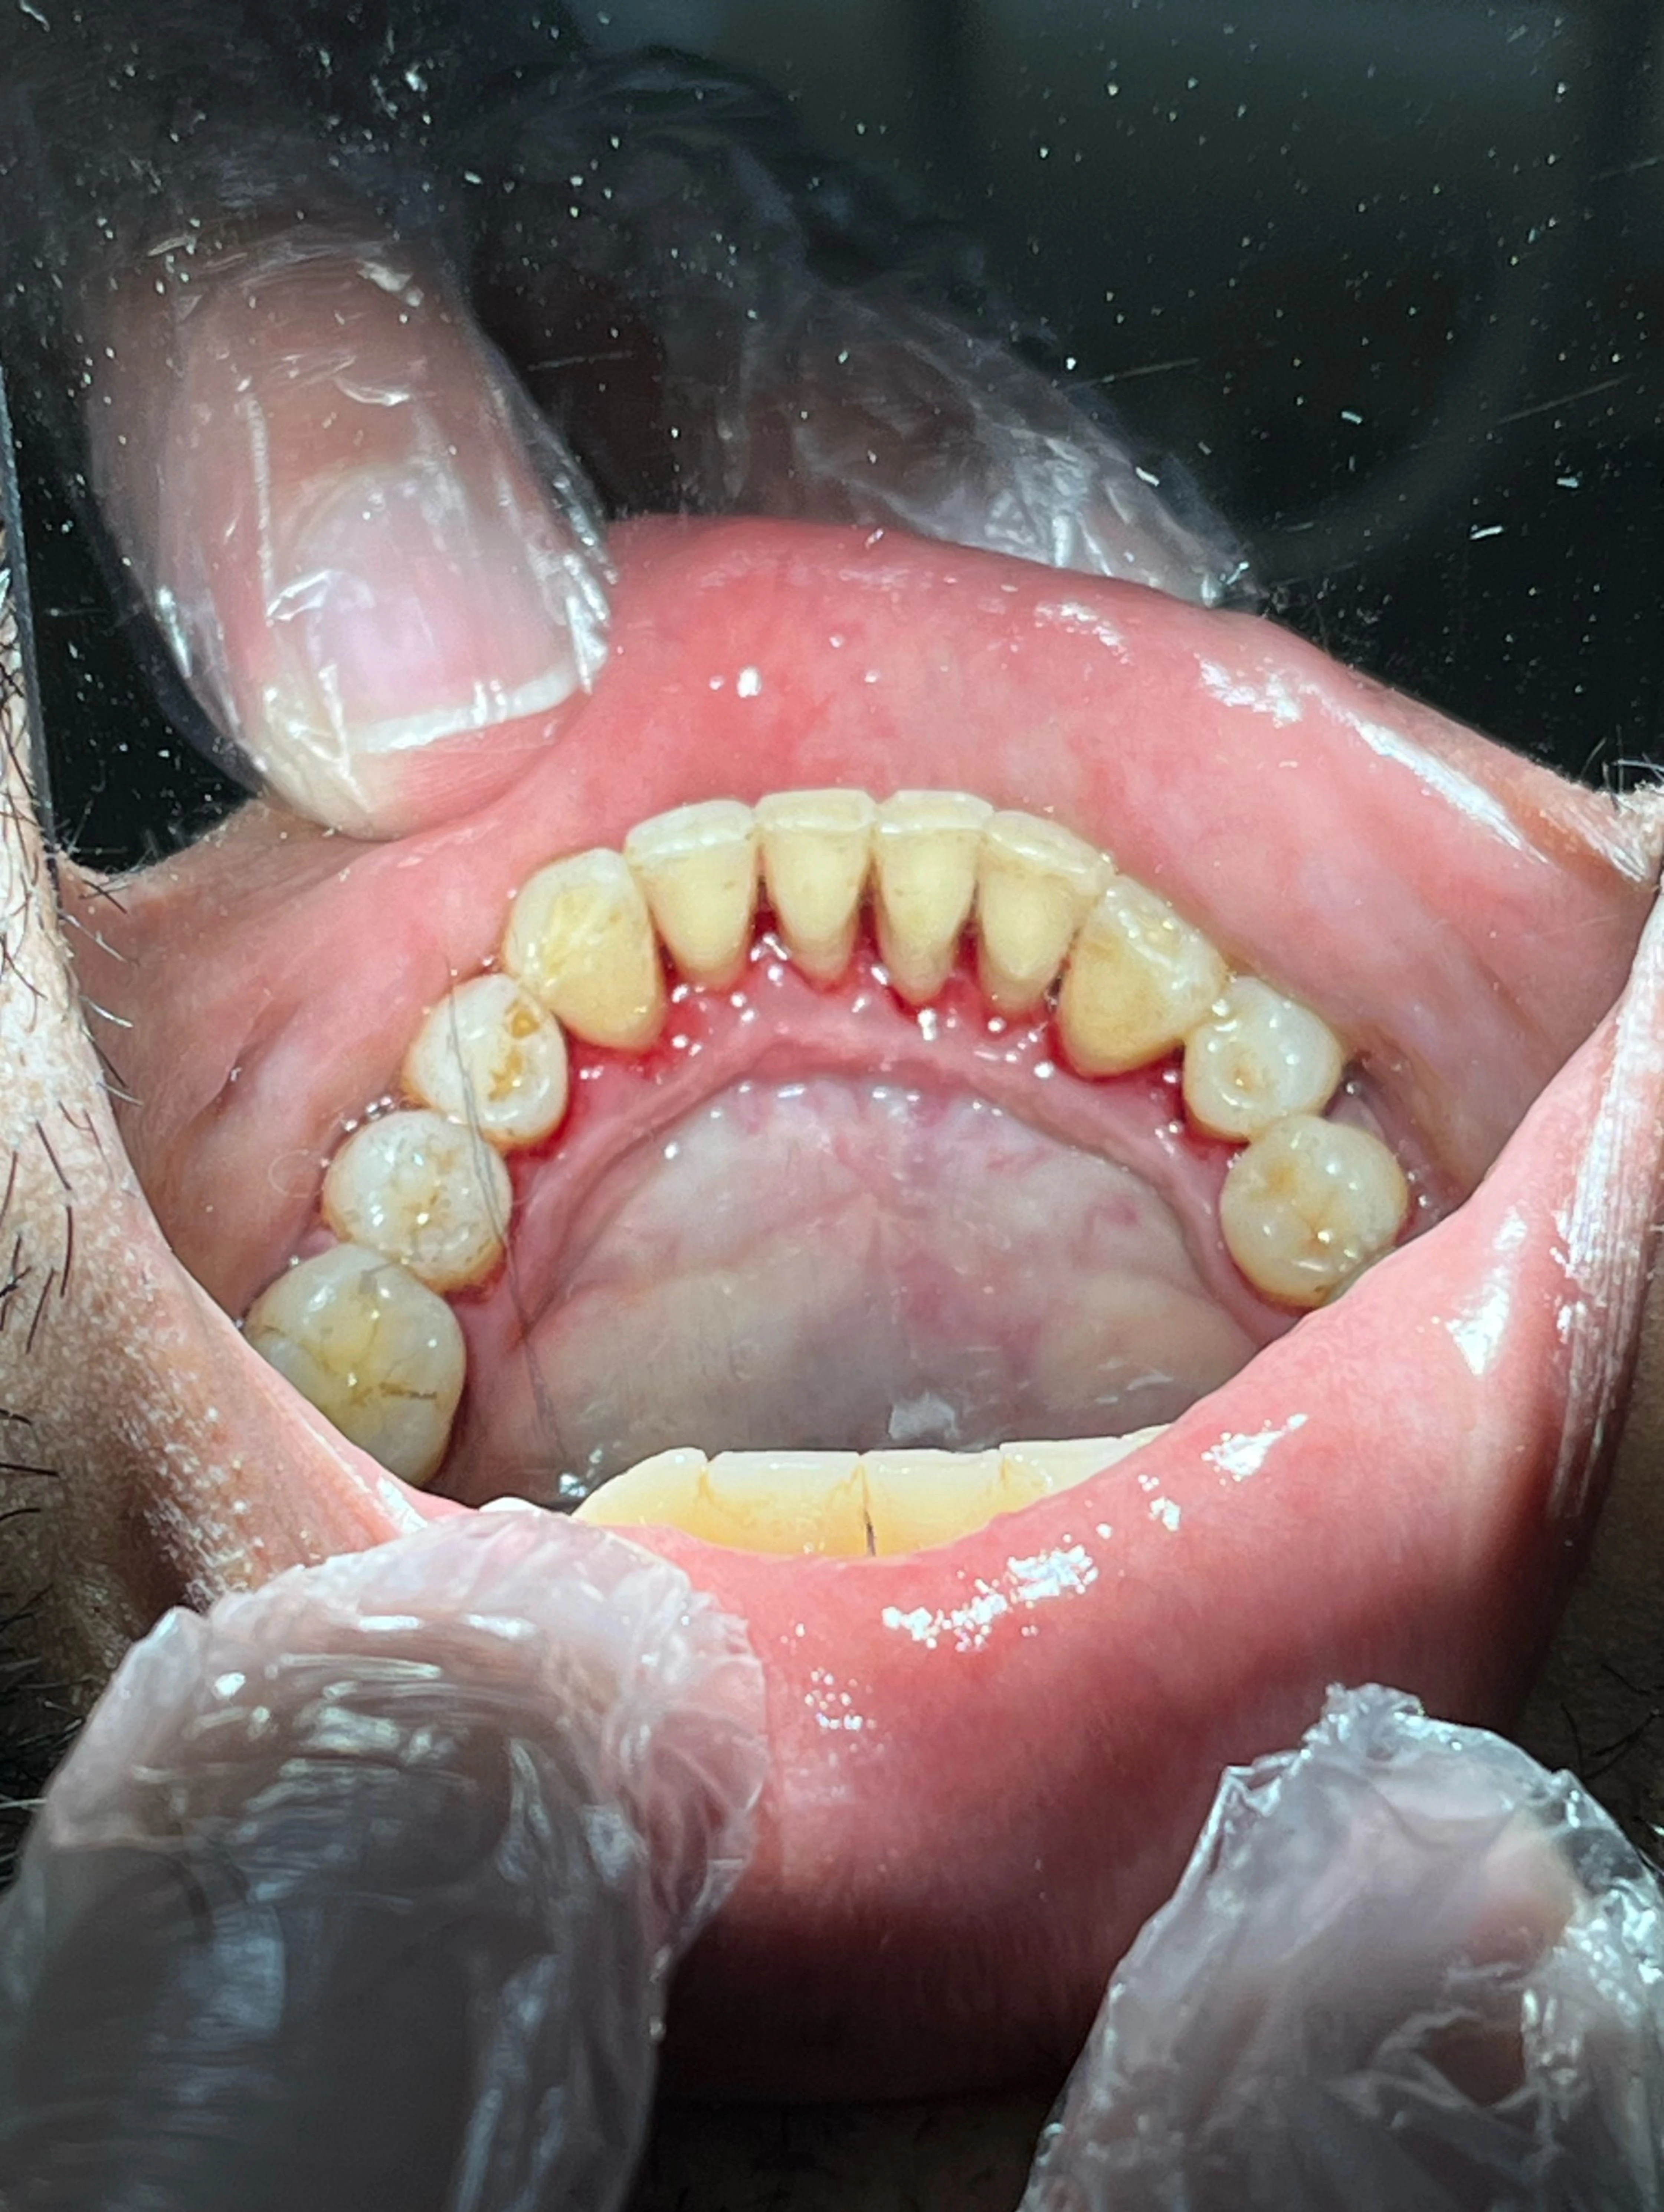

Scaling and polishing is a professional dental cleaning procedure designed to remove plaque, tartar (hardened plaque), and stains from your teeth.

Scaling involves the careful removal of plaque and tartar from the tooth surface and below the gum line using specialized dental tools. These deposits cannot be removed by regular brushing alone.

Polishing, on the other hand, is the final step where the teeth are smoothed and polished using a special paste. This not only makes your teeth feel clean and shiny but also helps prevent future plaque buildup.

Together, these steps leave your teeth cleaner, healthier, and visibly brighter.